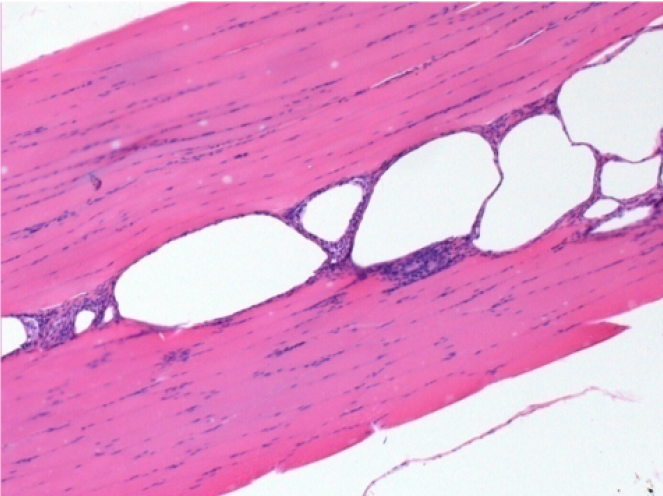

0.5 ml ( 5x 0.1ml) Endopeel SC Injection in the right subcutaneous pretibial area.

L:200x-Control-SC

R-D10-SC-200X